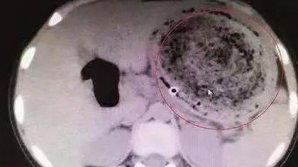

Тэги: волосы Умер парикмахер, который изобрел укладку волос Девочка шесть лет ела волосы и вырастила колтун в желудке Курьезно замерзшие волосы американки удивили Сеть Пожилой мужчина отрезал волосы спящей пассажирке в Китае Жительницу Индии признали тинейджером с самыми длинными волосами в мире Раскрыт вред от мытья головы В Туркмении парикмахерам запретили красить волосы мужчинам На Камчатке девочка пожертвовала косу на парики для больных детей (видео) Женщина облысела из-за стресса во время подготовки к свадьбе Цвет волос оказался связан с полом человека Китайский мальчик прошел пять километров по морозу, чтобы сдать экзамен Младенец почти лишился пальцев ног из-за волос матери Лысая Полина Гагарина ошеломила своим видом: фото Синяки и вырванные волосы: Женщины подрались за место в маршрутке Ученые: Голодание провоцирует рост волос Бизнесмен из Бельц остриг ребёнку волосы и написал на лбу "Я-вор" В Чечне отец обрил налысо 17-летнюю дочь после новости о скором замужестве Роскошная шевелюра новорождённой девочки сделала её звездой Reddit В Испании спасли 6-летнюю девочку, чьи волосы затянуло в фильтр для бассейна Пост больной девушки, которая не расчёсывалась 4 недели, собрал 200 тысяч лайков Видео: Разозлившийся детёныш панды напал на туристку Школа запретила ученику сбрить волосы в поддержку раковых больных Французский дизайнер создала часы из волос Российские ученые научились определять тяжесть стресса по волосам Реакция малыша, нашедшего чупа-чупс в своих волосах покорила пользователей Сети Настасья Самбурская опубликовала фото без волос Беременная Стоцкая перестала быть рыжей На шикарной свадьбе невесту обругали за грязные волосы Из кишечника российской школьницы достали 50-сантиметровое образование из волос Пассажирка самолета изобрела способ «быть ужасной на высоте 10 000 м» (ФОТО) 1 ABCDEFGHIJKLMNOPQRSTUVWXYZ IMPORTANTE ALTELE